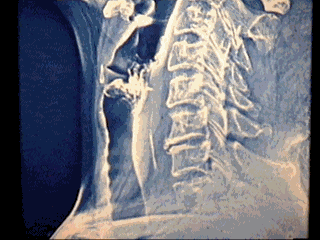

T.C. QUE CORRESPONDIO A UN

NI�O DE I 4 MESES DE EDAD,QUE PRESENTO DISFONIA Y ESTRIDOR MODERADO

DE 6 DIAS DE EVOLUCION.SE SOLICITO T.C. REPORTANDO CUERPO EXTRA�O

ALOJADO EN LARINGE, PROCEDIENDO A SU EXTRACCION. FOREIGN BODY IN

LARYNX , DISTRESS AND DISPHONIA OF ONE WEEK EVOLUTION DIAGNOSTIC

T.C. | |